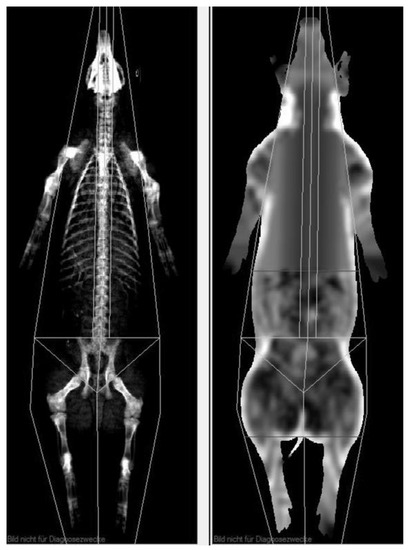

2.2.1. Magnetic Resonance Imaging

2.2.2. Dual Energy X-ray Absorptiometry